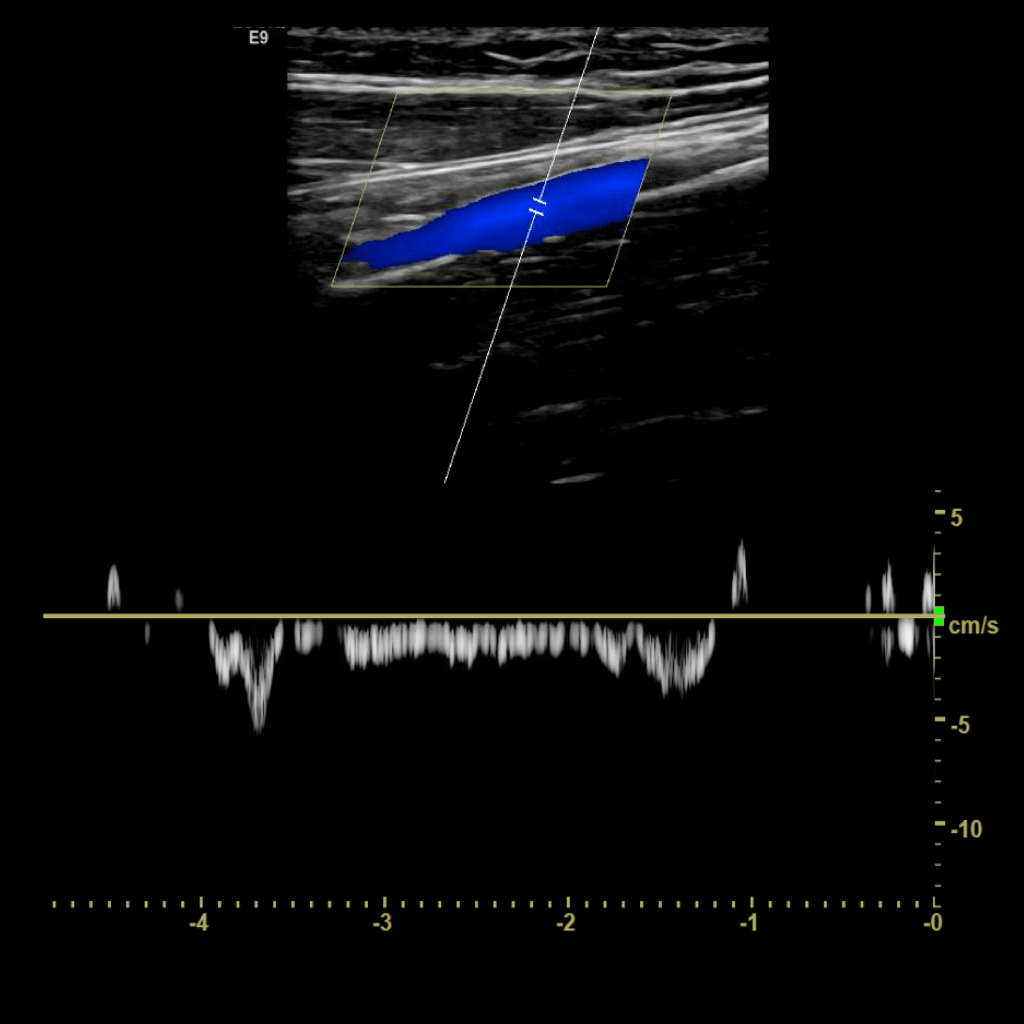

A typical scanning protocol includes transverse and sagittal images with and without color doppler and spectral wave analysis of the IJV, subclavian, axillary, brachial, basilic, cephalic, radial and ulnar veins. In my institution we include innominate and superior vena cava (SVC) in the vessels we interrogate.

Scan the internal jugular vein in grey scale, compression, color doppler and spectral doppler

Scan the subclavian vein in grey scale, color doppler and spectral doppler

Scan the axillary vein in grey scale, compression, color doppler and spectral doppler